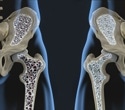

Bone mineral density test. Women over 65, anyone who has a fracture after age 50, and others with significant risk factors should get a bone density test. Bone density tests use xrays or sound waves to measure the strength of the bones. Bone density tests are safe, painless, and quick, and indicate the health of bones. Check with your health care professional about your risks and find out if you need a bone density test.